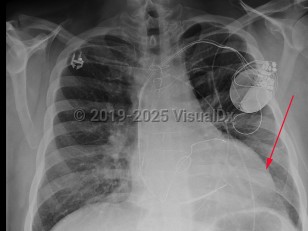

Chest pain, Pleural effusion, 50-59 year old Female

Hemothorax